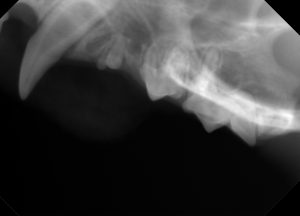

★別の歯も見た目では全くわかりませんが、レントゲンを撮ると一番右側に写っている歯の根っこの形が普通ではなかったです。無処置です。